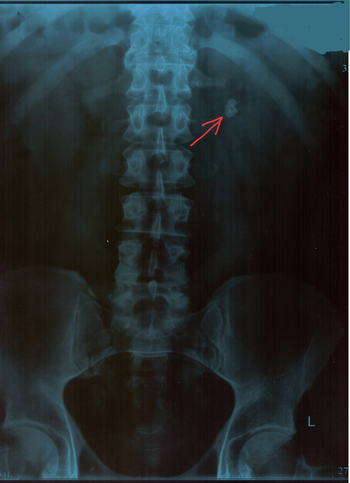

Хорошо, делаем [хотя бы] обзорную урограмму при хорошо подготовленном кишечнике и там видим такую «красоту» (фото 6).

Фото 6 — Урограмма